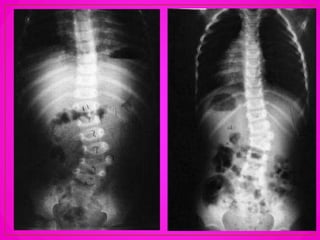

• El aumento de la lordosis

lumbar se observa en la

espondilolistesis, que significa

un desplazamiento de la

columna lumbar sobre el

sacro.